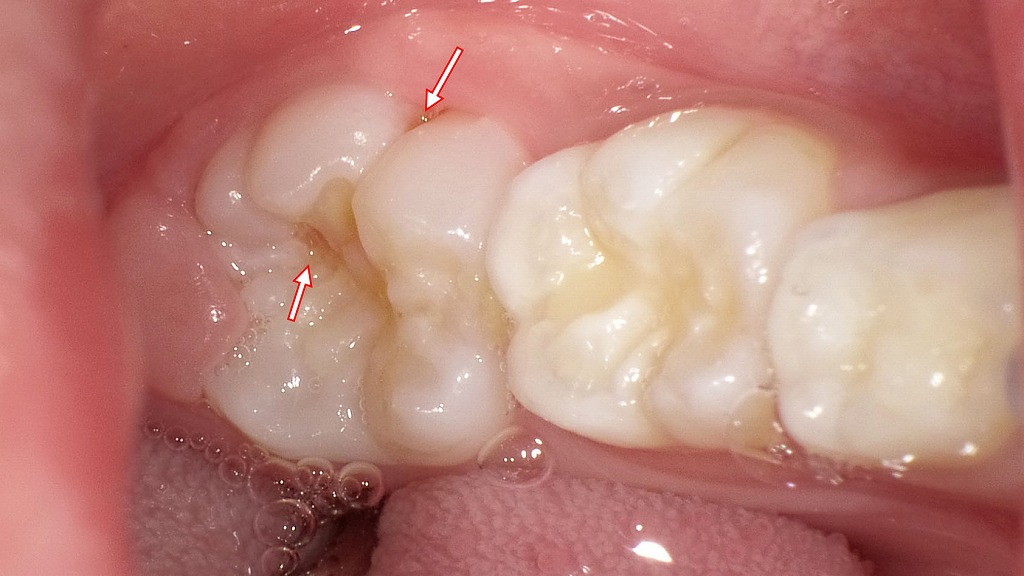

生えたての6歳臼歯にできた初期むし歯 ― レノビーゴによる予防ケアの重要性

えたばかりの6歳臼歯は、溝が深く歯質も未成熟なため、むし歯になりやすい状態です。画像では、溝の部分に初期むし歯が疑われる所見が見られます。

この時期は「削る治療」よりも、フッ素を効果的に補給し、歯を強くする予防ケアが重要です。0歳からレノビーゴのような低濃度フッ素配合スプレーを活用することで、再石灰化を促し、むし歯の進行を抑えることが期待できます。

生えたての6歳臼歯こそ、早期からの適切なケアが将来の歯の健康を左右します。